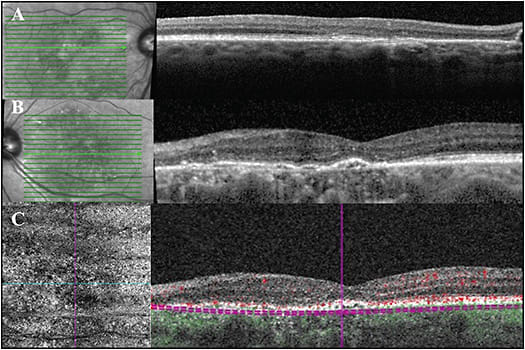

Clinical fundus exam demonstrated intermediate drusen of both eyes with pigment changes in the left eye and no hemorrhage. Figures 4A, 4B highlight the foveal cross-sectional OCTs of the right and left eye, respectively. The right eye demonstrates small drusenoid PEDs. This is notably overlying a thickened choroid with enlarged or pachyvessels. The left eye demonstrates SRF in excess to what would be expected for exudative AMD. There is also a confluent row of PEDS forming a double-layer sign.

OCT-A (Figure 4C) of the left eye, segmented at the level of the choriocapillaris, demonstrates Type 1 neovascularization at the nasal side of the PED. Note, cross-sectional flow overlay signals help to localize this to the sub-RPE space. The SRF has waxed and waned over 2 years, while maintaining stable vision of 20/50. Figure 4D demonstrates a spontaneous reduction in the amount of SRF.